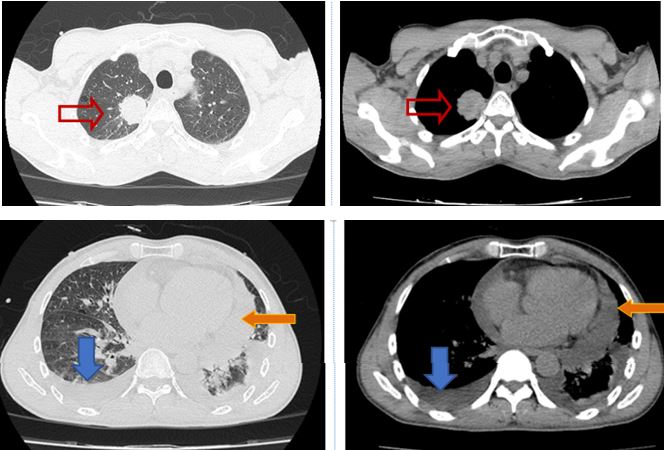

Dưới đây là hình ảnh PET/CT của bệnh nhân:

Hình 2: Hình ảnh hạch nách trái kích thước 1,2cm, giá trị max SUV=2,02 ( vòng tròn đỏ).

Hình 3: Hình ảnh hạch rốn phổi trái kích thước 0,9cm tăng hấp thu F-18 FDG, max SUV=4,05 (mũi tên đỏ).

Hình 4: Hình ảnh hạch rốn phổi phải kích thước 1cm và 0,9cm tăng hấp thu F-18 FDG, max SUV=4,17( vòng tròn vàng).